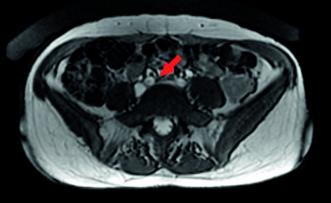

In unserer Anamnese der seit vielen Jahren bestehenden Unterbauchschmerzen zeigten sich lageabhängige Beschwerden, die im Tagesverlauf zunahmen und in die Leistengegend sowie den Oberschenkel ausstrahlten. Ergänzt wurde die Anamnese durch Feststellung einer Pollakisurie und Dyspareunie. In der angiologischen Diagnostik konnte mittels farbkodierter Duplexsonographie eine Nutcracker-Anatomie (Einklemmung der linken Nierenvene zwischen der oberen Darmarterie und der Bauchaorta) und eine May-Thurner-Anatomie (Kompression der linken Vena iliaca commuis durch die rechte Arteria iliaca communis) festgestellt werden (Abb. 4, 5). In der MR-Phlebographie fanden wir ausgeprägte parauterine Varizen und eine stark erweiterte insuffiziente Vena ovarica links (Abb. 6).

Die Diagnostik des Pelvic Congestion Syndroms setzt die interdisziplinäre Zusammenarbeit von Gynäkologie und Angiologie voraus. In der gynäkologischen Abklärung können mittels transvaginaler Sonografie mit Valsalva Krampfadern im Bereich der inneren Geschlechtsorgane erkannt und ein begründeter Verdacht auf PCS ausgesprochen werden. Nach Ausschluss möglicher Differenzialdiagnosen (Endometriose, Uterus myomatosus, Harnwegsinfekt etc.) erfolgt die Überweisung zur weiteren Abklärung an die Gefässmedizin. Die angiologische Diagnostik umfasst primär die farbkodierte Duplexsonographie, um Obstruktionen des tiefen Venensystems auszuschliessen (May-Thurner Anatomie, Nutcracker-Anatomie, Obstruktionen der Vena cava oder Beckenvenen). Weiter werden in der MR-Phlebographie des Abdomens und Beckens die Pathologie der Beckenvenen bestätigt oder Alternativdiagnosen ausgeschlossen.